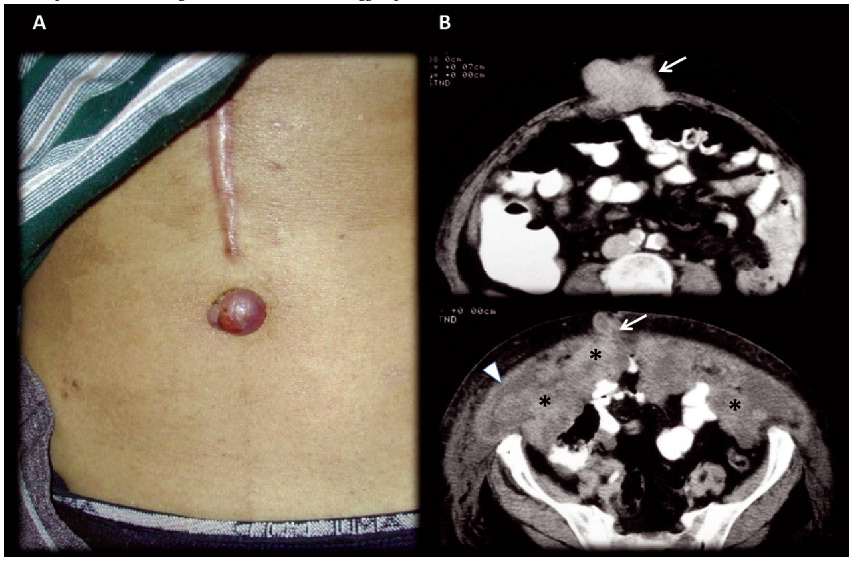

This nodule refers to a non-sensible palpable, periumbilical nodule bulge which color varies from violaceous to reddish brown that may appear as vascular structure. Occasionally skin ulcerations or fissures with even hematic, serous or purulent discharge can be observed. The lesion diameter rarely exceeds 5 centimeters, even so, it can be larger and simulate an umbilical hernia (Figures 2, 3, 4, 5 and 7).6

A) Picture of the umbilical lesion; B) Contrast enhanced MDCT axial slices, in portal-venous phase: Extensive gastric neoplasm recurrence with omental involvement (omental cake) (*); Diffuse nodular peritoneal thickening and ascites (arrow head), suggests peritoneal carcinomatousis; metastatic umbilical nodule (SMJN) (arrow).